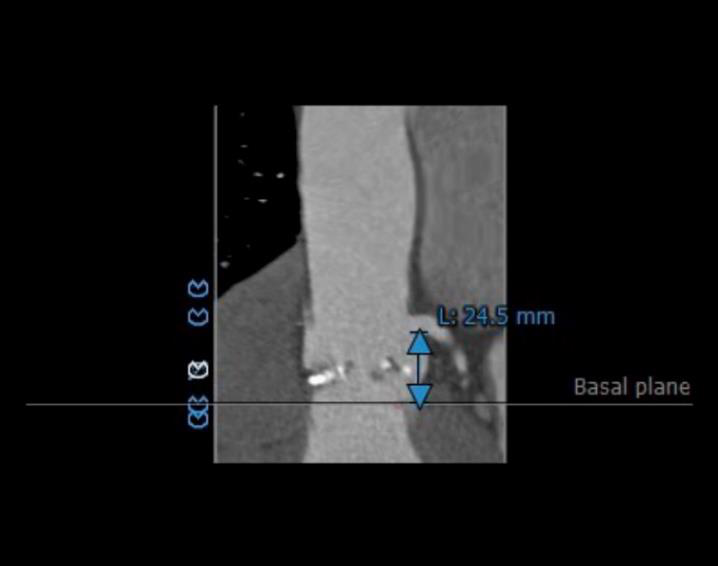

左右冠开口高度可,右冠多发钙化,依据瓦氏窦宽度和瓣叶长度预估右冠风险较小,左冠存在堵塞风险。

瓦氏窦内径、窦管交界内径偏小。升主内径尚可,主动脉瓣环与水平面夹角可,主动脉弓角度与宽度可。

①瓦氏窦整体形态偏小,钙化程度较轻。

主动脉根部造影提示瓦氏窦整体形态偏小,决定给予冠脉保护